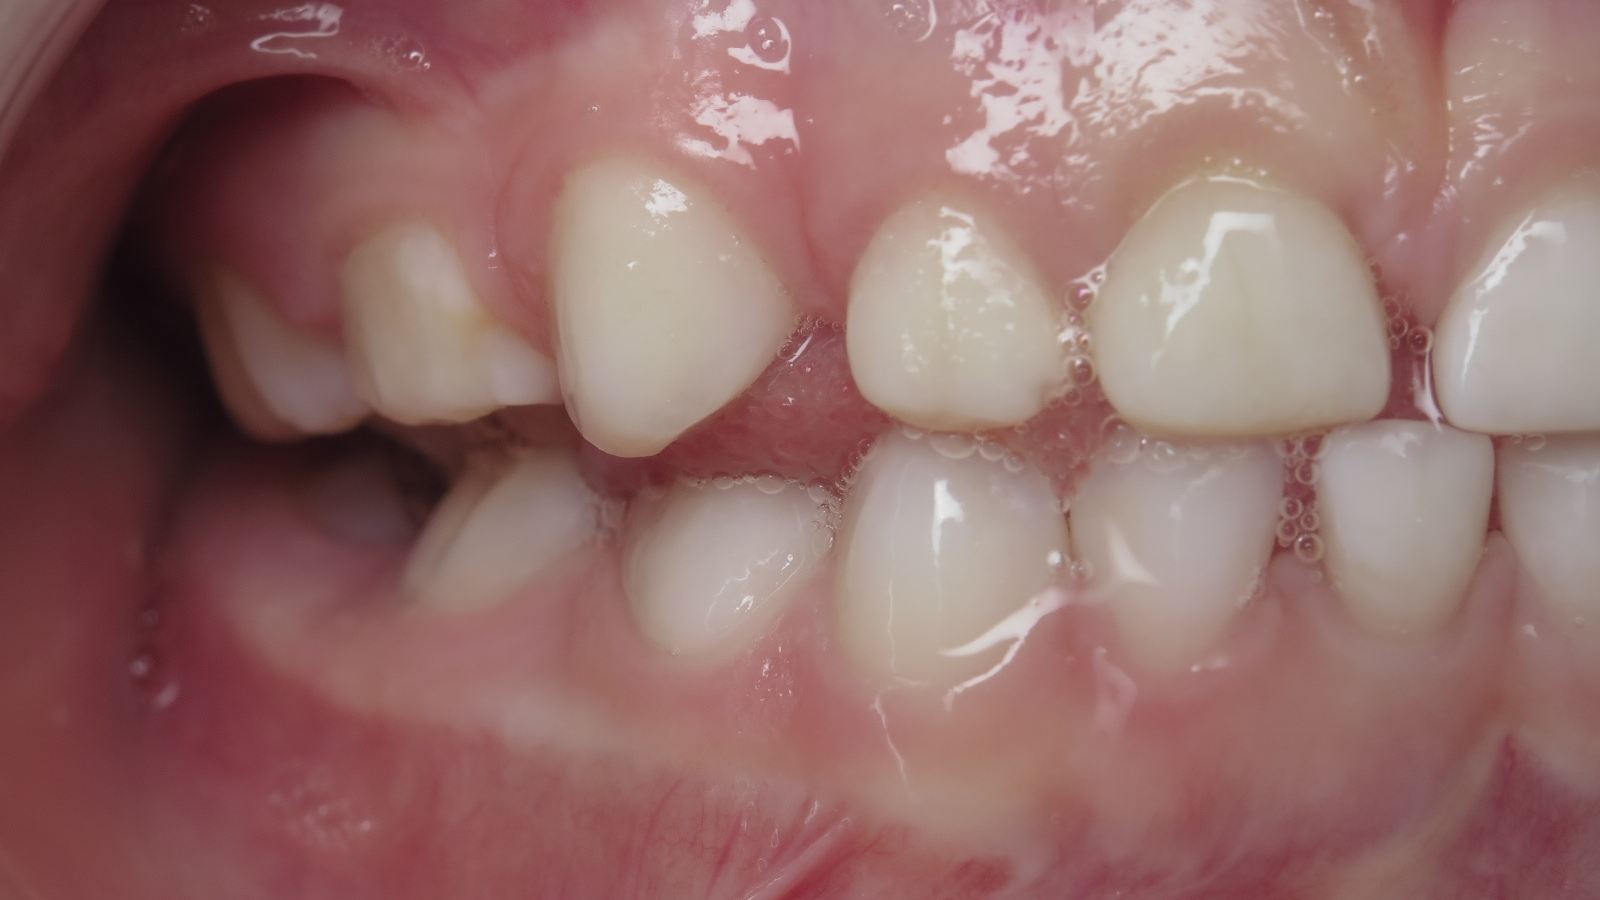

7.inversé droit 4 ans

inversion des dents postérieur coté droit

bilan début et en cours de traitement